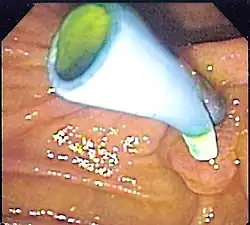

Endoscopic image of a biliary stent seen protruding from the ampulla of Vater at the time of duodenoscopy

Pancreatic and biliary stents provide pancreatic and bile drainage from the gallbladder, pancreas, and bile ducts to the duodenum in conditions such as ascending cholangitis due to obstructing gallstones.

Pancreatic and biliary stents can also be used to treat biliary/pancreatic leaks or to prevent post-ERCP pancreatitis.[12]

In the case of gallstone pancreatitis, a gallstone travels from the gallbladder and blocks the opening to the first part of the small intestine (duodenum). This causes a backup of fluid that can travel up both the bile duct and the pancreatic duct. Gallbladder stones can lead to obstruction of the biliary tree via which gallbladder and pancreas enzymes are secreted into the duodenum, causing emergency events such as acute cholecystitis or acute pancreatitis.[12]

In conditions such as ascending cholangitis due to obstructing gallstones, these stents play a crucial role. They help in maintaining the flow of bile and pancreatic juices from the gallbladder, pancreas, and bile ducts to the duodenum1. Biliary stents are often used during endoscopic retrograde cholangiopancreatography (ERCP) to treat blockages that narrow your bile or pancreatic ducts. In cases of malignant biliary obstruction, endoscopic stent placement is one of the treatment options to relieve the obstruction. Biliary drainage is considered effective, particularly in bile duct conditions that are diagnosed and treated early.[12]